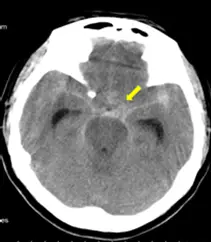

觀察提供的無顯影劑腦部電腦斷層 (Non-contrast Head CT) 影像,可見箭號指向的異常高密度 (hyperdense,即呈現白色影像) 訊號。這些出血訊號並未形成緊貼顱骨內緣的明顯半圓形或雙凸形團塊,而是呈現不規則形狀,順著大腦皮質的輪廓,填滿了腦溝 (Sulci)、腦裂 (Fissures,如外側裂 Sylvian fissure) 或是腦基底池 (Basal cisterns) 的空間。這種血液如同樹枝狀或星狀散佈於腦部表面皺褶內的視覺特徵,代表血液積聚於蜘蛛網膜與軟腦膜之間的空間,為典型「蛛網膜下腔出血」的影像學發現。

- C. 蛛網膜下腔出血 (Subarachnoid hemorrhage, SAH): 血液積聚於蜘蛛網膜與軟腦膜之間的空間 (即充滿腦脊髓液的空間)。在 CT 上表現為高密度訊號瀰漫性地填滿腦溝、腦裂及腦池。與本題箭號所指的影像特徵完全吻合,為正確選項。

根據影像分析,出血位置位於腦膜的最內層空間,順著大腦的自然皺褶 (腦裂、腦溝與腦池) 蔓延,此解剖位置即為蛛網膜下腔。這與硬膜外腔、硬膜下腔於顱骨內緣形成的局部佔位性血腫 (Mass effect) 外觀截然不同,且並未侷限於腦室腔內。綜合解剖位置與典型影像特徵,故最佳解答為 (C) 蛛網膜下腔出血。